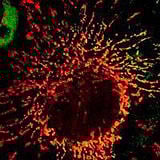

Our bodies are composed of as many as 60 trillion cells, which maintain life by performing diverse roles under a highly regulated system. If genetic mutations occur in these cells or if they are subjected to stress, the internal regulatory mechanisms can become abnormal. This disrupts the balance between cell "life" and "death," leading to the development of various diseases. For example, when cells that should have died due to genetic damage continue to live, they can cause diseases such as cancer. Conversely, the abnormal death of cells can lead to conditions like Alzheimer's disease.

We are investigating the mechanisms that regulate this balance between "life" and "death." Specifically, we aim to elucidate the pathogenic mechanisms of cancer and Alzheimer's disease. We do this by investigating, at the molecular level, the changes that occur within cells when genes (or their mutant versions) thought to be involved in regulating cell "life" and "death" are expressed in normal cells, or conversely, when those genes are disrupted. At the same time, we are also aiming to develop therapeutic drugs for cancer and Alzheimer's disease. Microorganisms produce numerous compounds with diverse structures and unique physiological activities, and quite a few are already in use as pharmaceuticals. Therefore, we are searching for compounds, primarily from microbial products, that can suppress the action of genes involved in the onset of cancer and Alzheimer's disease. We are also investigating the mechanisms by which these discovered compounds suppress the action of disease-related genes to explore their potential for therapeutic application.